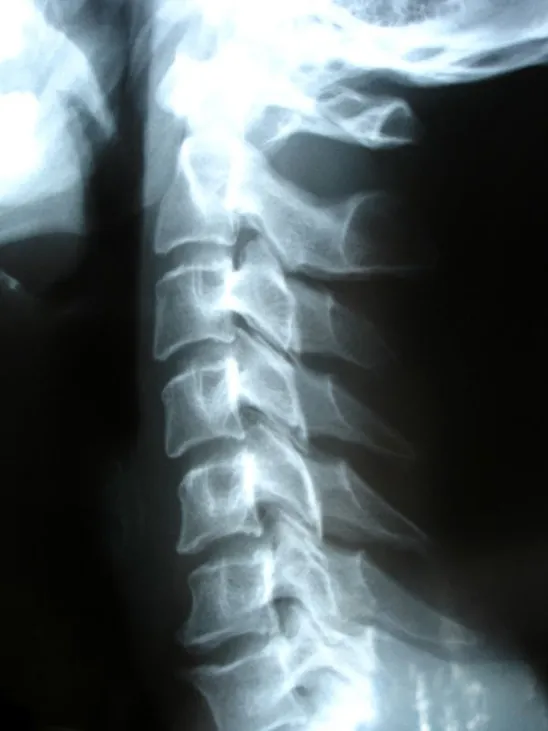

When you’re in pain—especially after an accident or with long-term joint problems—the mystery is often hidden in the way your body moves, not just how it looks at rest. Standard X-rays are helpful, but sometimes they can miss the real source of trouble if it only shows up during certain motions. That’s where digital motion X-ray technology shines. At Advanced Physical Medicine of Yorkville in Yorkville, IL, we believe in giving you answers, not just images. Here are some clear answers to the most common questions we get about this game-changing diagnostic tool.

A digital motion X-ray (DMX) is a specialized imaging technique that creates a real-time video of your joints or spine while you move. Instead of a single snapshot, DMX captures the entire sequence—helping our auto accident chiropractor snear you see issues invisible on traditional static X-rays.

Traditional X-rays take still pictures, which can miss problems only present during movement. MRIs are great for soft tissue but also require you to be still. DMX lets our chiropractors near you watch ligaments, bones, and joints in action, revealing instabilities, misalignments, or abnormal motions in real time.